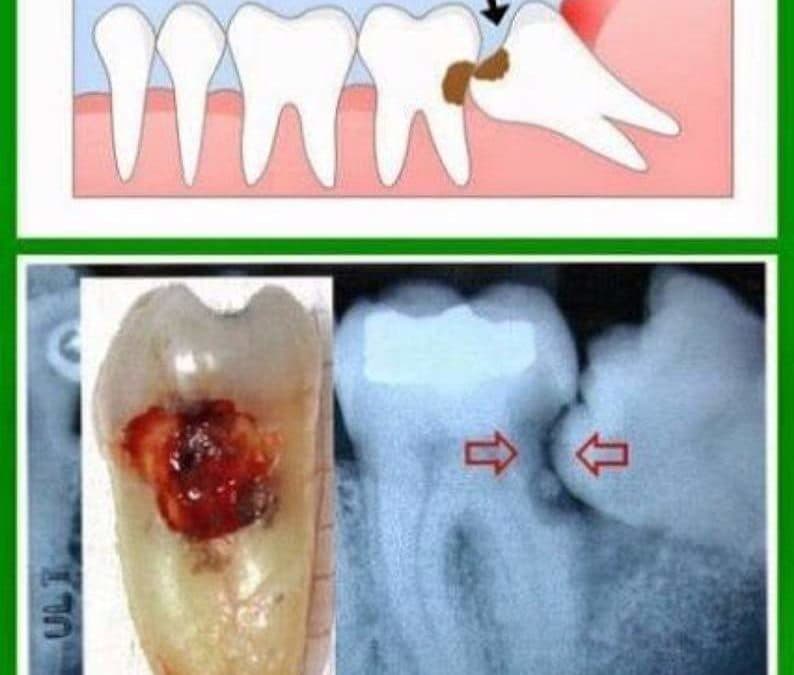

Sometimes wisdom teeth don’t have enough space to grow properly and end up being only partially erupted. They become difficult to clean and their position can lead to problems on adjacent teeth. In some cases, early removal can avoid unnecessary complications, pain and possible infection. At Millcroft Dental Care, your dentist is trained and experienced in detecting any wisdom teeth concerns, and he/she will address them and advise you of the necessary treatment. Please call, Tel: 905 315 9888 and book a consultation if you have any questions or concerns regarding your wisdom teeth.